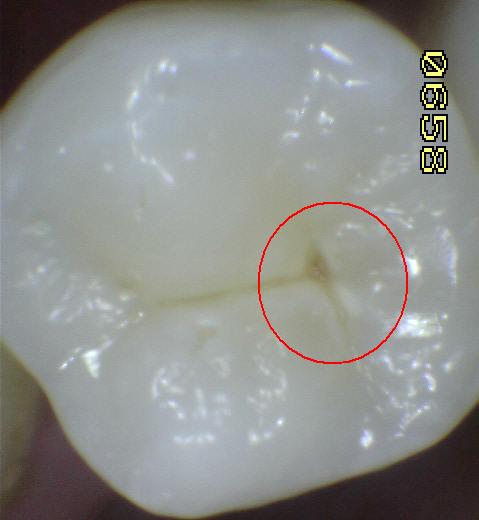

Hay  4 tipos morfológicos de fosas y fisuras:

1: En forma de "U"

2: En forma de "V"

3: En forma de "Y"

4: En forma de "Botella de Coca-Cola"

Una morfología de la fisura estrecha, con forma de botella de "Coca-Cola" genera un nicho ecológico ideal para la colonización de cualquier bacteria productora de ácidos. Al no poder remover en forma períodica dicho biofilm de una zona tan estrecha, el ataque ácido genera una lesión cariosa en la dentina, con un aspecto de esmalte intacto a la inspección visual, o sea un típico código 3 y 4 de ICDAS Completo. (Caries Moderada para el ICDAS COMBINADO)

Por este motivo es importante realizar el sellado de las fosas y fisuras de molares y premolares cuando comienza su erupción dentaria, como método de prevención eficaz de caries.

Imagen digital que representa la microfiltración y penetración del sellante realizado.

Microfotografía: Muestra como el sellador obtura la caries subyascente, evitando su avance.

Código 3 (Caries moderada) in vitro. Los códigos 3 in vivo debe ser sellado para evitar el avance del proceso carioso. (MNO)

Código 4 (Caries moderada) in vitro. Los códigos 4 in vivo deben ser tratados en forma operatoria con preservación dental (MOPD), porque presentan dentina infectada.